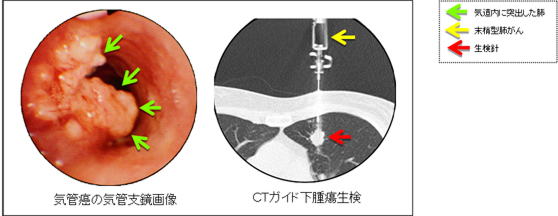

確定診断をするためには画像で見えるできもの(腫瘍または転移臓器)の一部(組織)を採ってきて顕微鏡で調べる必要があります。体の外側から組織を採る方法としては、気管支鏡検査、CTガイド下生検などがあります。気管支鏡検査は口から柔らかい管(気管支ファイバー)を気道に入れて体の内側から肺の組織を採る方法です。CTガイド下針生検は、CT画像で観ながら体の表面から針を刺し入れ肺または転移した臓器の腫瘍組織を採取する方法です。どちらの検査も体に負担があり合併症を起こす場合があるため3日間程度の入院が必要です。(図5)に肺門部肺がん(気管癌)の気管支鏡画像と末梢型肺がんのCTガイド下腫瘍生検画像を示しました。

図5 気管支鏡画像とCTガイド下生検画像